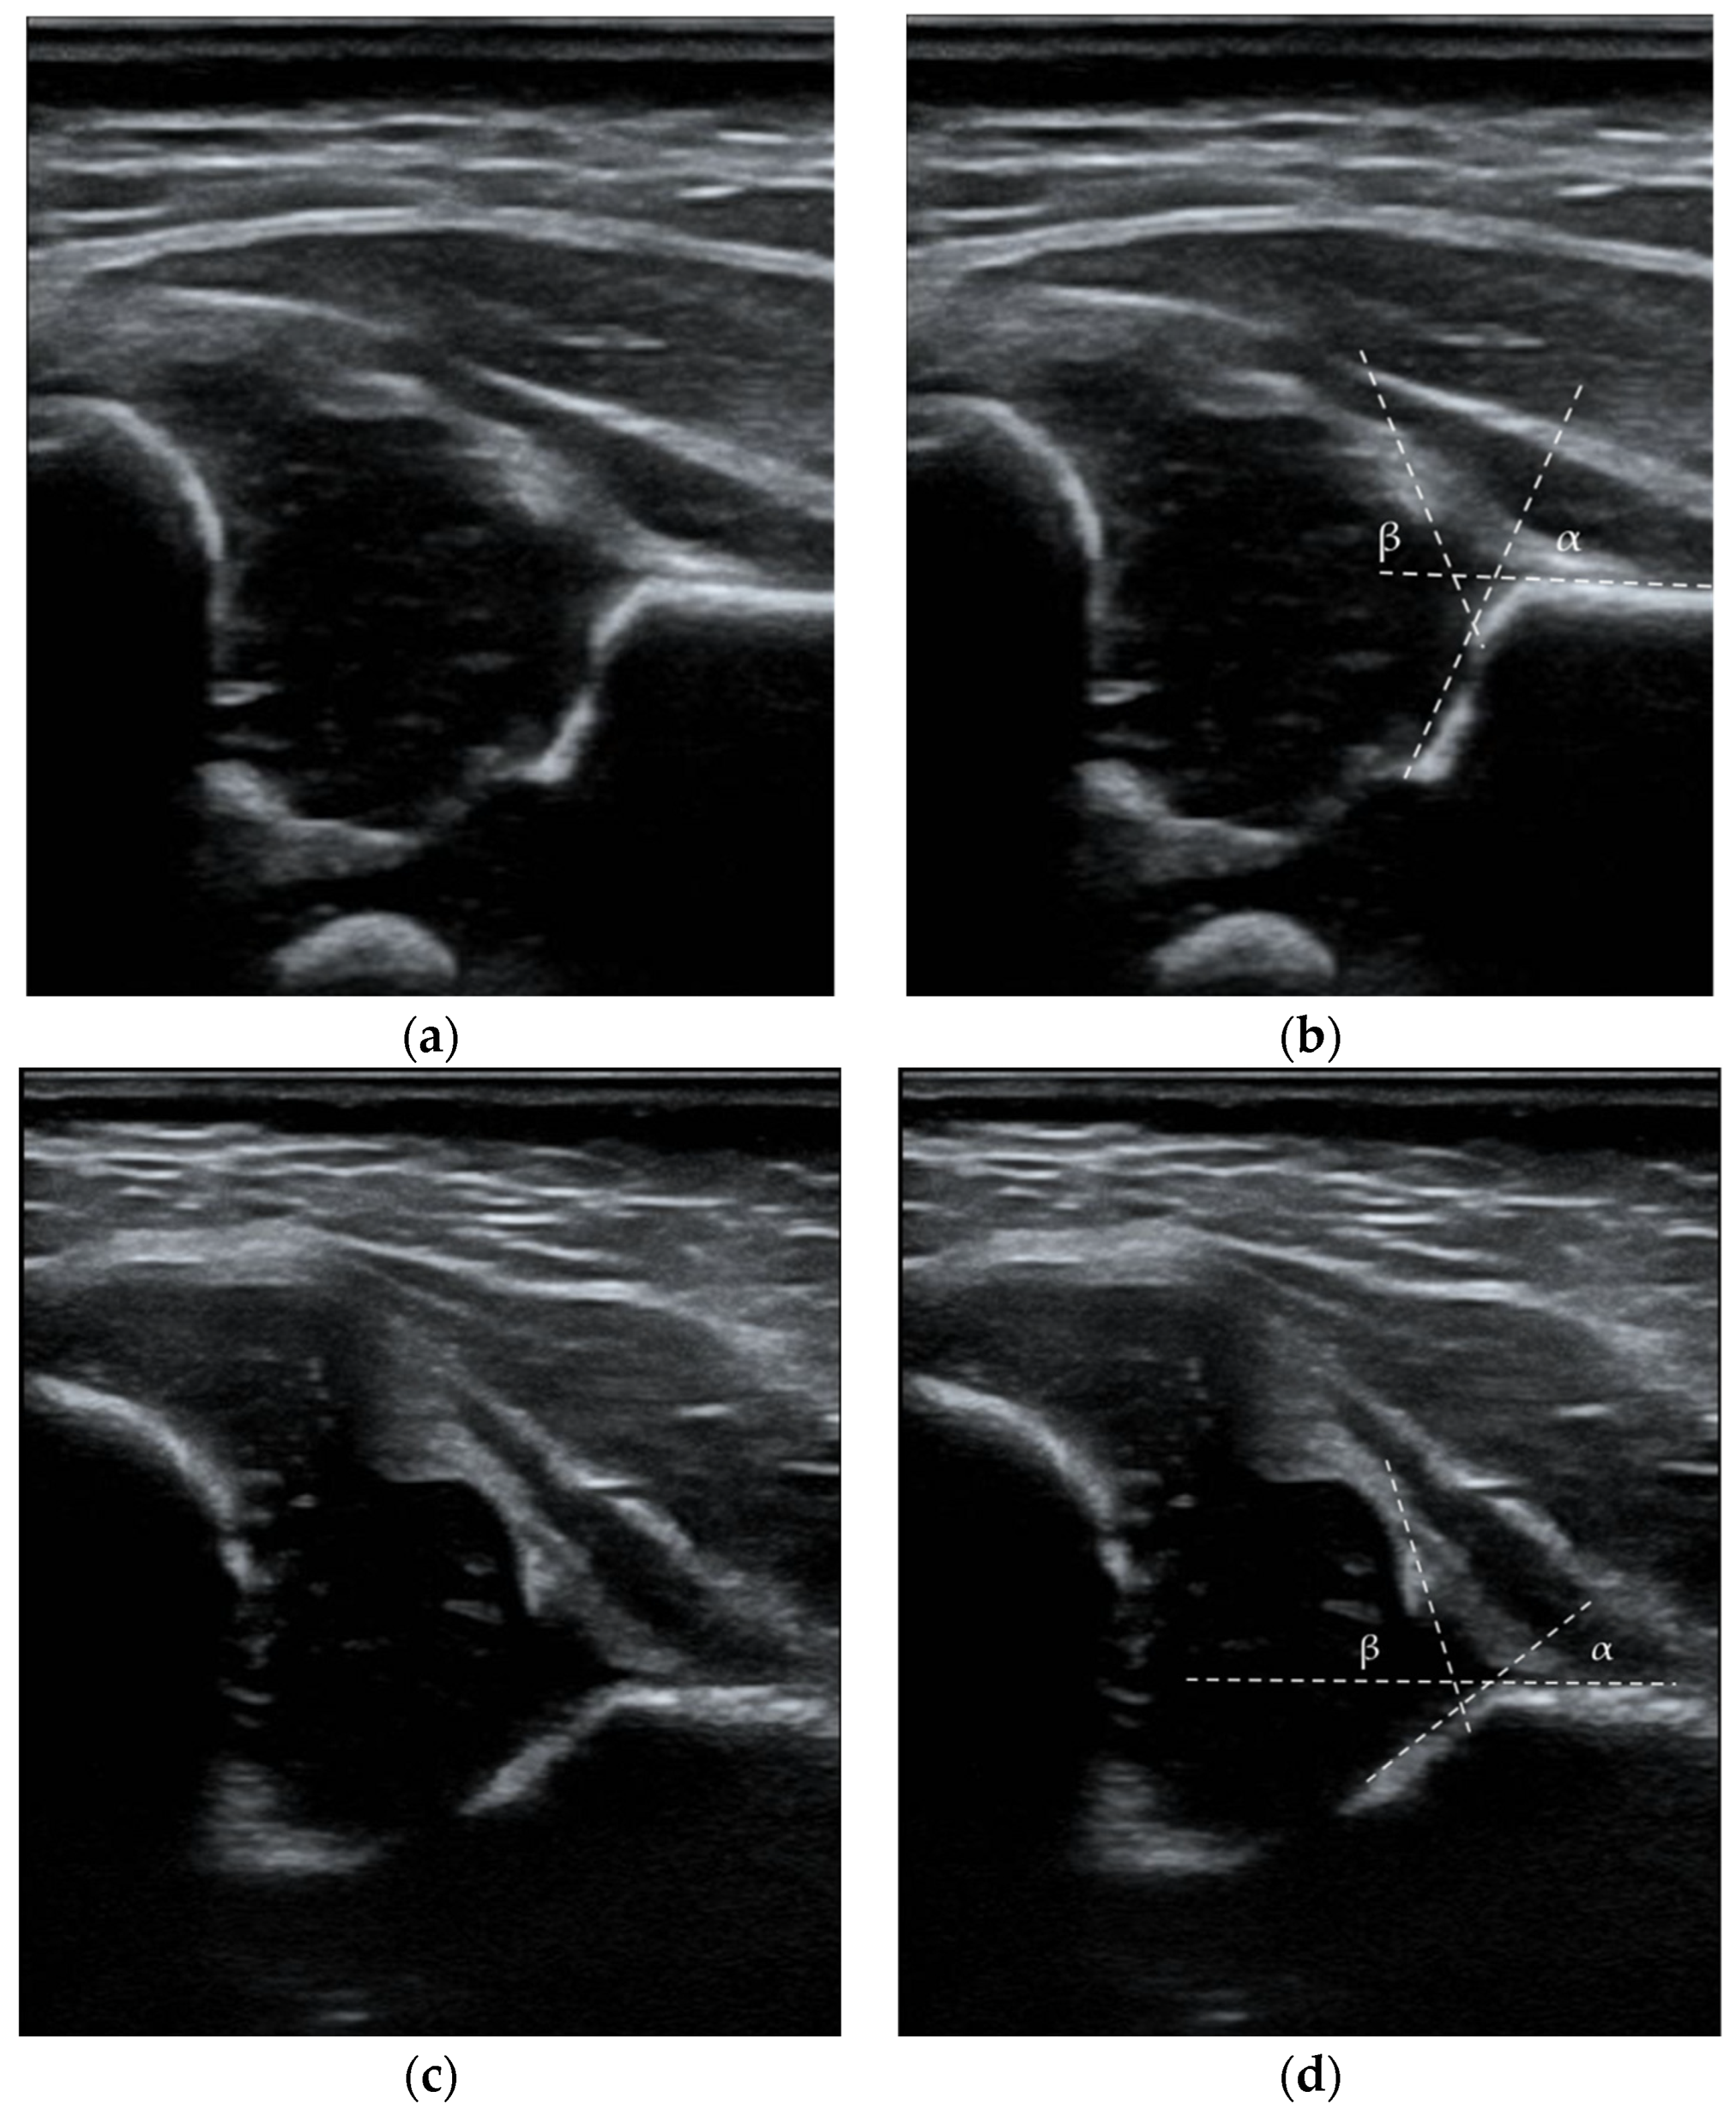

According to Graf’s classification, the diagnostic criteria for DDH were type IIa (-), IIb, IIc, D, III, and IV images. Type IIa hips before 6 weeks of age were monitored and treated only in the absence of signs of sufficient maturation (IIa (-) or IIb) [28]. Figure 2 presents ultrasound images from the data set with the measurements outlined. Our clinic recommends the first ultrasound examination at 6 weeks of life. In the case of a positive physical examination at birth or risk factors, ultrasound is recommended in the first weeks of life. The second control visit is also recommended for healthy children at 12 weeks. The history of hip orthopedic examination included the maximum abduction angle value for each hip joint, the Ortolani test, the Barlow test, and the Galeazzi test. The abduction asymmetry was defined as a difference of 20° or more. Articular noises on physical examination such as “clicks” or “creaks” were not classified as pathological findings [29]. The record included the name, national identification code, age, and date of visit. Information on possible risk factors such as female sex, abnormal presentation, high birth weight, term of birth, MuP, mode of delivery, diabetes, positive family history and coexisting medical conditions in children was collected.

Figure 2.

Ultrasound images with the measurements outlined: (a,b) Type IB, hip joint according to Graf, α = 68° β = 67°; (c,d) Type III, hip joint according to Graf, α = 42° β = 73°. White lines represent the base line, the bony roof line, and the cartilaginous roof line.